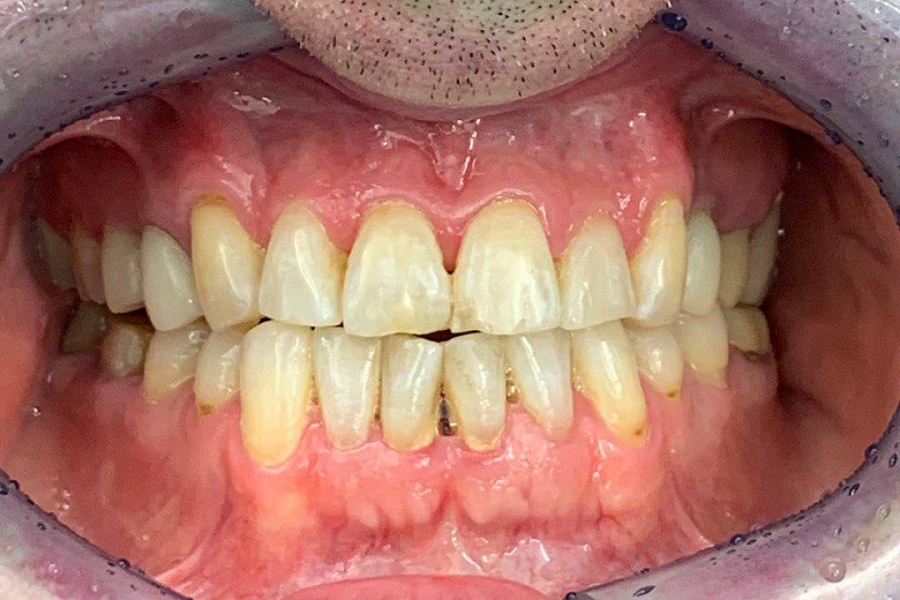

Наш постоянный клиент, который настаивал только на лечении кариеса. Несмотря на ряд проблем: стираемость зубов, перекрестный прикус, который и вызывал увеличение стираемости, пациент не хотел делать комплексную работу.

В итоге из-за неправильного прикуса стираемость зубов прогрессировала и нам удалось убедить пациента заняться данной проблемой серьезно.

1. Восстановлена правильная позиция зубов с помощью ортодонтического лечения под наблюдением гнатолога, но в связи с высокой стираемостью этого было недостаточно.2. Была проведена ортопедическая реабилитация ортопедическими конструкциями с восстановлением высоты нижней трети лица и формы стертых зубов.

В результате мы получили сохранность ситуации , которая не ухудшается дальше. Лицо стало более молодым и подтянутым. Пациент перестал скрипеть зубами и стирать свои собственные зубы.